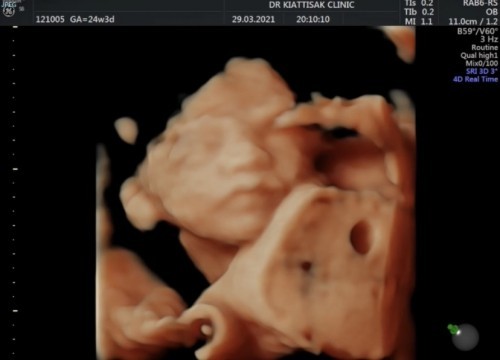

ฉันอุ้มท้องนะ หน้าไม่เหมือนแม่เลย😂

ลูกหน้าเหมือนพ่อไปหมดเลยค่ะ แม่แอบนอยด์55555555555555 ขนาดลุงหมอยังแซวเลยงับบ ผมหน้าได้พ่อหมดเลย😂😂😂😂🤍🤍💝💝

24 w ค่ะ